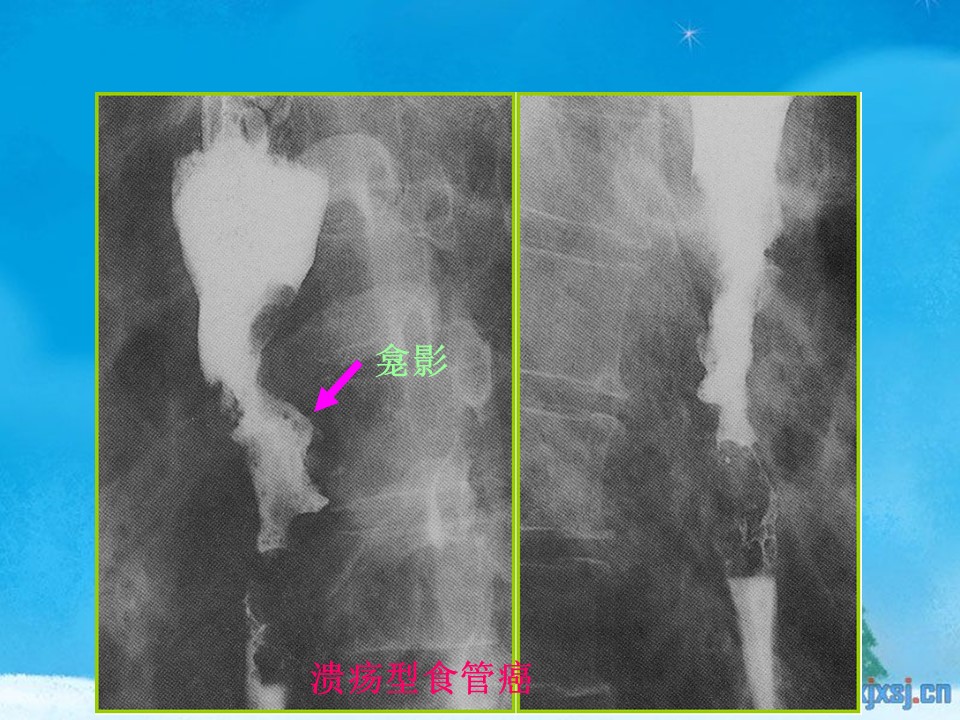

“腹部、盆腔影像诊断学PPT” 的相关文章